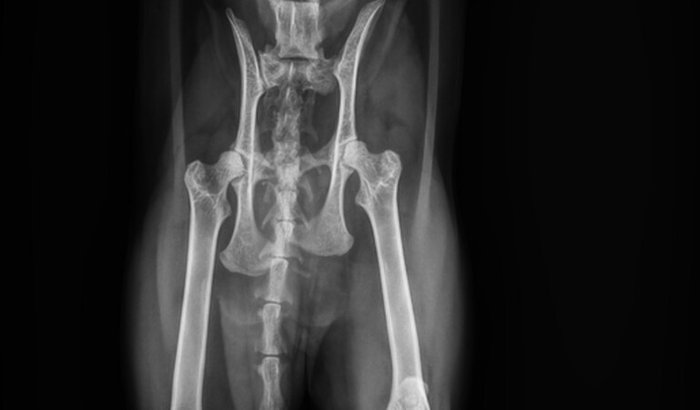

Na madrugada de domingo, a Revoada sofreu um trauma sério. Não sabemos exatamente o que aconteceu — se foi atropelamento, queda ou outro acidente — mas o impacto fraturou o osso coxal. Ela precisa de uma cirurgia urgente, com anestesia e exames, e o valor total gira em torno de R$ 4.000.